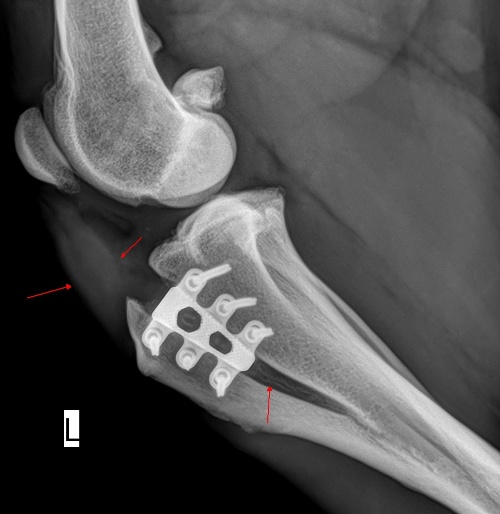

Wie bei anderen Operationen auch, halten Sie Ihren Hund nach einer Operation mit TTA RAPID bitte für mindestens 6 Wochen an der Leine. Denn im Vergleich zum Menschen vergisst der Hund, dass er operiert worden ist, sobald er keine Schmerzen mehr hat. Seien Sie sich jedoch immer bewusst, dass es in Ihrem Hund unmittelbar nach der OP so aussieht:

TTA RAPID® Röntgenbild direkt nach der Operation →

Der Knochen hat noch nicht seine ursprüngliche Stabilität erreicht. Stöckchen werfen, Ball spielen, Begrüßungstänzchen, Sprünge und Raufen mit anderen Hunden sind für 12 Wochen absolut tabu. Auch sind Treppenläufe und -stürze (!) zu vermeiden. Vermeiden Sie, dass Ihr Hund ungebremst durch die Wohnung läuft. Ihr Hund braucht Schonung. Am besten stellen Sie sich vor, wie Sie sich verhalten würden, wenn Sie selbst am Knie operiert worden wären.